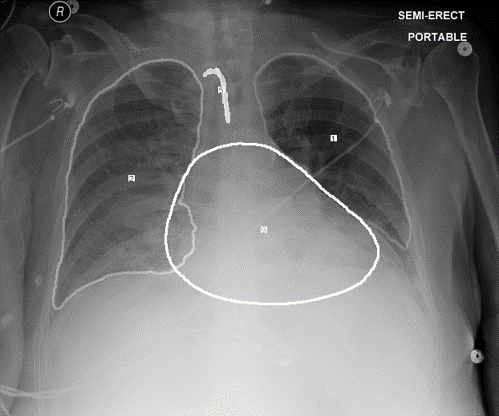

We present qualitative results in \figurereffig:qual1,fig:qual2 and \figurereffig:qual4 for MAIRA-Seg-Frontal and MAIRA-Seg-Multi, respectively. We present the target report and predicted findings of the baselines and corresponding proposed MAIRA-Seg methods. In the reports, we highlight the phrases selected for further analysis (gray) in the target findings, and the corresponding errors (red) and correct predictions (green). The image labelled as “current image with mask pseudolabels” is only for illustrating the mask pseudolabels used along with the CXR image in the MAIRA-Seg architecture, where the masks in green, red, yellow, blue, light-blue, white correspond to right lung, left lung, NGT, CVC, ETT, and heart respectively.